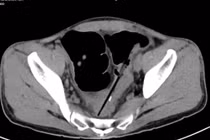

Trung tâm Phẫu thuật tiêu hóa - Bệnh viện Bạch Mai vừa phẫu thuật một trường hợp người bệnh nuốt nhiều dị vật gây biến chứng thủng đại tràng. Người bệnh được chẩn đoán mắc hội chứng Pica (hội chứng thích ăn các đồ vật không phải thức ăn).

Nguyên nhân trong ổ bụng bệnh nhân có nhiều dị vật là do người bệnh được chẩn đoán mắc hội chứng Pica, hay còn gọi là hội chứng thích ăn các đồ vật không phải thức ăn.